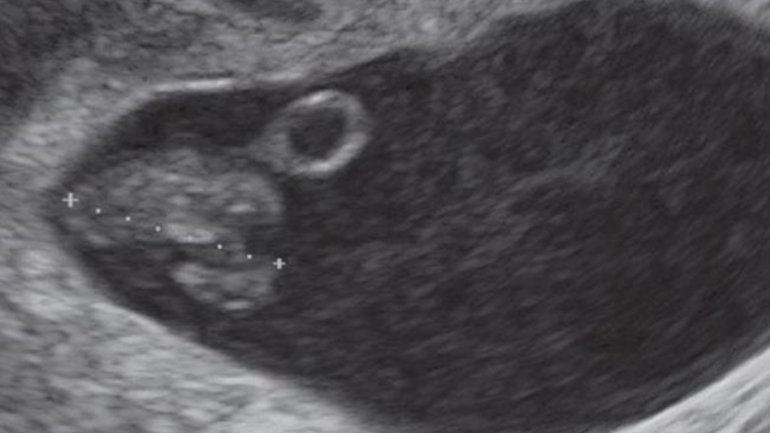

Ultraschall 14. SSW

Auf diesem Bild sieht man eine Zwillingsschwangerschaft mit zwei Fruchtblasen. Die meisten Zwillinge, ob eineiig oder zweieiig, haben eine eigene Fruchtblase und eine eigene Plazenta. Selten teilt sich die befruchtete Eizelle bei eineiigen Zwillingen erst spät in der Entwicklung in zwei Embryos auf, was zu einer gemeinsamen Fruchtblase und Plazenta führt. Ab dieser Woche kann man mit etwas Glück das Geschlecht des Babys erkennen.